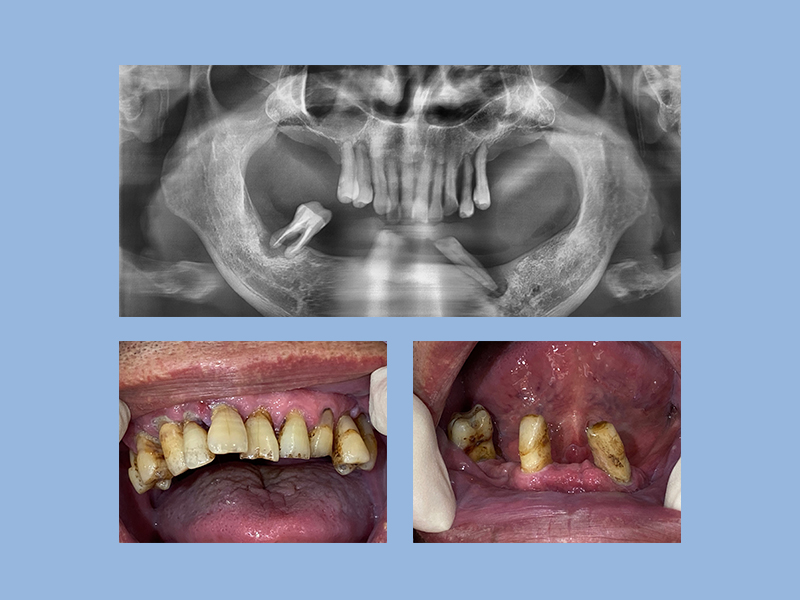

古院長不僅是每年新病例數達80位以上的 #隱適美白金精英級,更是 #中壢區 排名數一數二矯正醫師,矯正前需先給醫師評估後,再制定專屬客製的矯正計畫,搭配3D口內掃描機,影像資訊透過全球同步的數據計算,矯正者可以清楚了解牙齒每週位移的軌跡。

同時,醫師從影像中做技術評估,設計以隱適美豆豆、局部鋼絲、拉橡皮筋等工具,確實且正確的達到矯正進度。要完成整體牙齒外觀的整齊度,以及完美的咬合結果,憑藉著經驗值高的醫師專業判斷。